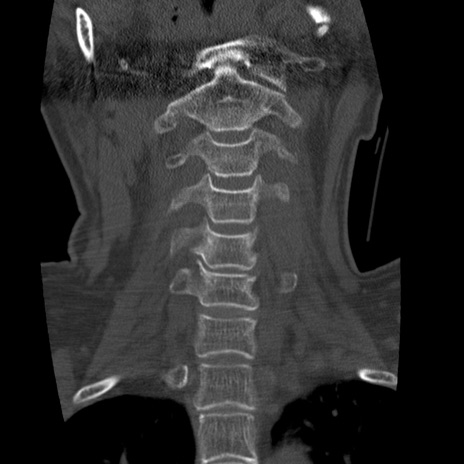

症例50 頚椎CT(冠状断像)

頚椎CT